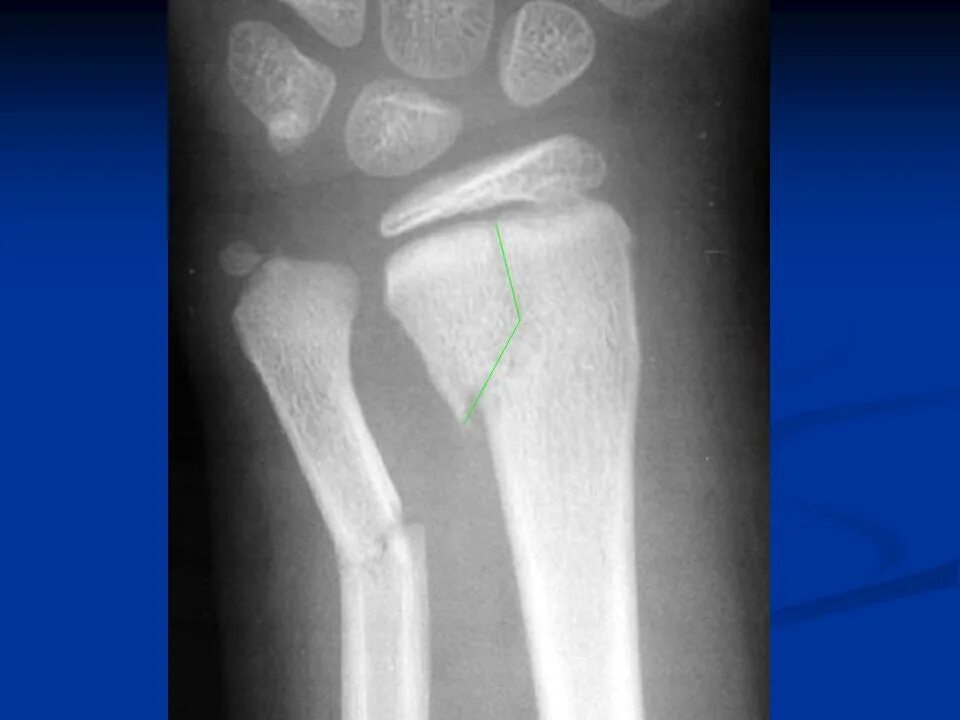

Перелом без причины